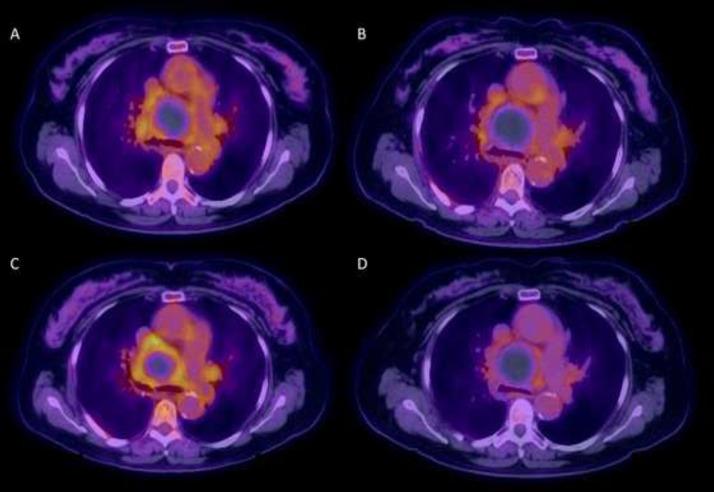

Bronchial artery aneurysm and pseudoaneurysm is a rare but life-threatening diagnosis due to catastrophic complications from rupture. Prompt detection and management is key to prevent complications. CT angiogram and digital subtraction angiography are preferred diagnostic imaging modalities. Being very uncommon, these entities can be misdiagnosed as a nonspecific mediastinal soft tissue mass, which can lead to delay in diagnosis and inappropriate or delayed management. We present a case of 72-year-old woman with incidentally detected large bronchial artery pseudoaneurysm, incorrectly classified as mediastinal malignancy at outside facility, receiving follow-up exams for 2 years, before correct diagnosis and management.

支气管动脉动脉瘤和假性动脉瘤是一种罕见但危及生命的诊断,因为破裂会引发灾难性并发症。及时检测和处理是预防并发症的关键。CT血管造影和数字减影血管造影是首选的诊断成像方式。由于非常罕见,这些病变可能被误诊为非特异性纵隔软组织肿块,从而导致诊断延迟以及治疗不当或延误。我们报告一例72岁女性病例,其偶然发现巨大支气管动脉假性动脉瘤,在外院被错误分类为纵隔恶性肿瘤,接受了2年的随访检查,最终才得以正确诊断和处理。